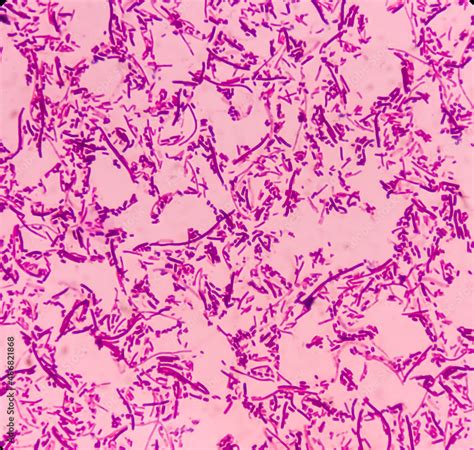

La fiebre tifoidea es una enfermedad infectocontagiosa aguda, generalizada y potencialmente mortal, causada por la bacteria Salmonella Typhi. Este bacilo gram negativo, perteneciente a la familia Enterobacteriaceae, es un importante patógeno humano. A nivel mundial, se estima que la fiebre tifoidea afecta a millones de personas anualmente, causando un número significativo de muertes, especialmente en países en vías de desarrollo.

El diagnóstico de la fiebre tifoidea se basa principalmente en el aislamiento del microorganismo. El hemocultivo se considera el "gold standard". La sensibilidad del hemocultivo es mayor durante la primera semana de enfermedad, por lo que su repetición puede ser necesaria. Los cultivos de heces u orina tienen menor valor diagnóstico, ya que los portadores sanos pueden presentar resultados positivos. En este caso, la repetición del hemocultivo, especialmente en el contexto de un escalofrío y antes de iniciar la antibioticoterapia, fue crucial para confirmar el diagnóstico. Es importante destacar que el volumen de sangre recolectado para el hemocultivo es una variable pre-analítica crítica para la recuperación del microorganismo.